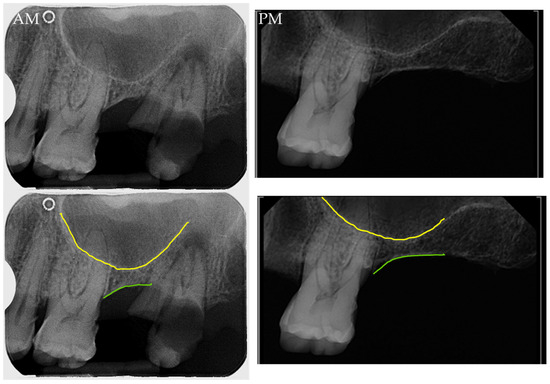

The comparison between antemortem panoramic radiographs and postmortem periapical radiographs is commonly performed in cases utilizing the maxillary sinus. In these cases, only the lower part of the maxillary sinuses can be compared (Figure 2).

Figure 2. Comparison between an antemortem panoramic radiograph fragment (AM) and postmortem periapical radiograph (PM) of the right maxillary premolar and molar area. The inferior border (or the floor) of the maxillary sinus is highlighted in yellow, and the 1st and 2nd premolars are labeled as PM1 and PM2, and the mesial alveolar portion of the molar is highlighted in pink. This comparison depicts consistent morphologies between the AM and PM radiographs, where the relationship of the inferior part of the maxillary sinus with the dental roots is key for the comparison. Source: Department of Applied Forensic Sciences at Mercyhurst University casework.

The maxillary sinus has been widely researched and used for human identification purposes due to its morphological variation and the clear visualization in several radiographical modalities such as panoramic, AP/PA cranial projections, Waters and lateral projections, as well as periapical radiographs. Although some research has suggested the influence of sex in the maxillary sinus volume, statistical analyses did not show significant differences between males’ and females’ data [39]. Maxillary body contour and septal pattern provide useful data for the postmortem vs. antemortem comparisons. Maxillary sinus morphological changes may occur after posterior tooth loss and as a result of sinus lift procedures prior to dental implant surgery, so that extractions and sinus bone graft surgery should be considered as a potential source of inconsistencies due to the sinus pneumatization [42,43,44]. In comparisons using the maxillary sinus, it is of high importance to rely not only on the sinus morphology but also on the relationship of the sinus floor with other anatomical structures such as the dental roots or the alveolar bone (Figure 7).

Figure 7. Comparison of the antemortem (AM) and the postmortem (PM) periapical radiographs, where the floor of the maxillary sinus is highlighted in yellow and the lower limit of the maxillary bone in the alveolar region is highlighted in green. Although the third molar is present in the AM and missing in the PM image, the sinus morphology and relationship with the first molar and the distal maxillary bone is consistent in both images. Additionally, the relationship between the sinus floor and the first molar’s root is maintained in the AM and the PM images. Source: Department of Applied Forensic Sciences at Mercyhurst University casework.